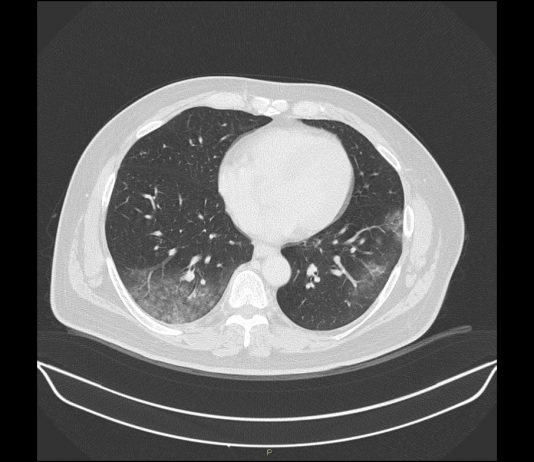

Uomo 57 anni, nessuna comorbidità nota.

Febbre e tosse non produttiva.

Leucocitosi. Insufficienza respiratoria ipossemica e ipocapnica.

Sospetto contatto con soggetti zona rossa. Tampone positivo NCOV 19.

HRTC Torace